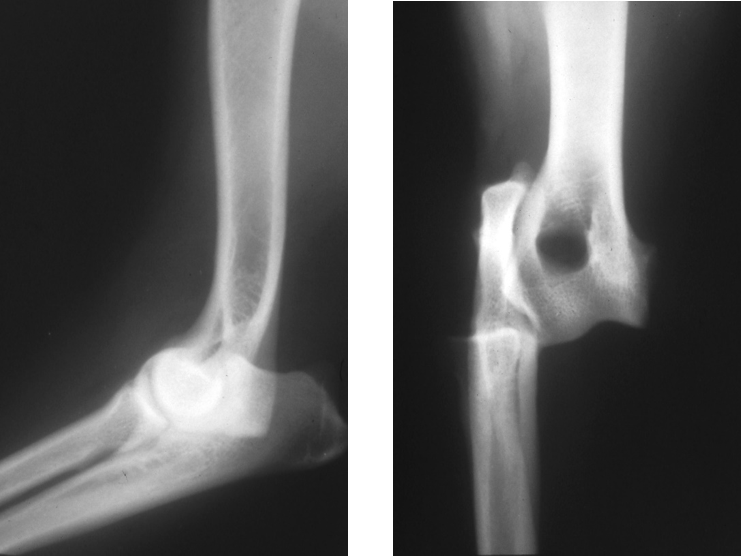

Discuss this radiograph?

Hip dysplasia, cranial acetabulum edge increased opacity

Discuss this radiograph

Bone infection – surrounding has increased opacity